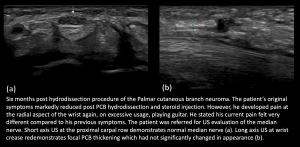

- Post Carpal Tunnel Release (CTR) surgery, Palmar Cutaneous Branch (PCB) neuroma and Flexor Carpi Radialis (FCR) tenosynovitis

Fig 14: POST CTR SURGERY PALMAR CUTANEOUS BRANCH (PCB) NEUROMA AND FCR TENOSYNOVITIS PCB neuroma and PCB hydrodissection with steroid injection

Fig 15: POST CTR SURGERY PALMAR CUTANEOUS BRANCH (PCB) NEUROMA AND FCR TENOSYNOVITIS Normal Median Nerve at Carpal tunnel; Persistent PCB neuroma